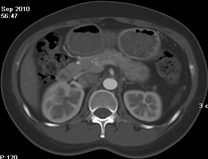

目前臨床對于16層CT的認可主要集中在三維成像領域上的突破.在16層CT的產品平臺上,常規(guī)掃描就能實現(xiàn)滿足三維成像的要求,因此16層也被稱為三維CT,三維成像給臨床診斷帶來了更精確更豐富的診斷信息,我們以臨床為例:

如上圖所示,相鄰的三張軸位圖像未見明顯異常,根據(jù)傳統(tǒng)軸位圖像很難得到準確的臨床診斷。

同一病人利用容積數(shù)據(jù)進行三維處理后,高品質MPR和三維圖像上則清晰顯示了縱向排列的腹腔干與腸系膜上動脈相鄰近,血管發(fā)生變 異,近端血管閉塞,為臨床提供了精確的診斷信息。

從上面的例子可以看到,能否為臨床提供高品質的三維影像成為了16層CT的核心價值,而東芝新一代的 全景三維16層CT擁有最為  先進的3項核心技術,在16層核心價值上的表現(xiàn)自然值得期待。